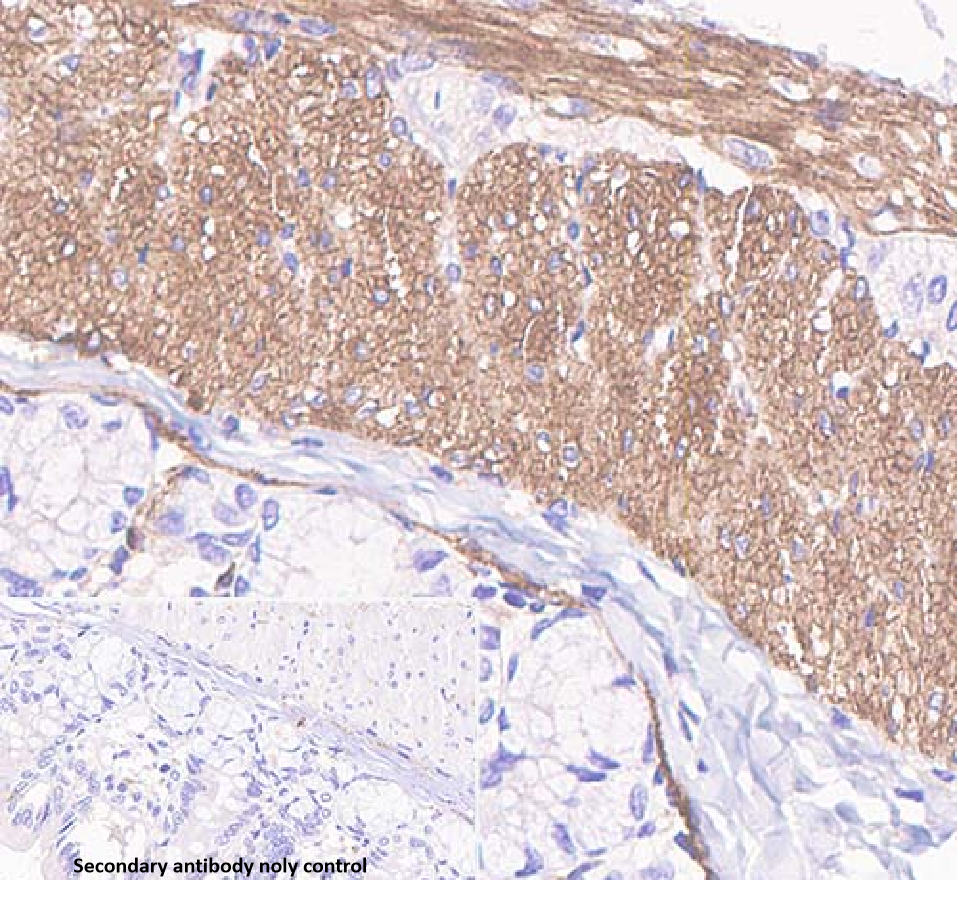

Positive control: Heart/uterine fibroid

Antigen retrieval: Heat retrieval (citrate)

Vinculin is a membrane cytoskeletal protein and a component of the focal adhesion complex, involved in the connection of integrin adhesion molecules to the actin cytoskeleton. The absence of vinculin affects a range of cellular functions, including disrupting the formation of the vinculin complex and inhibiting cell adhesion and spreading. The absence of vinculin reduces cell spreading, thereby decreasing stress fiber and focal adhesion formation, and inhibiting the extension of lamellar pseudopodia.

Vinculin antibody reagents can specifically bind to Vinculin molecular antigens. Immunohistochemistry kits containing Vinculin antibody reagents are suitable for the auxiliary diagnosis of diseases related to cell adhesion and migration.